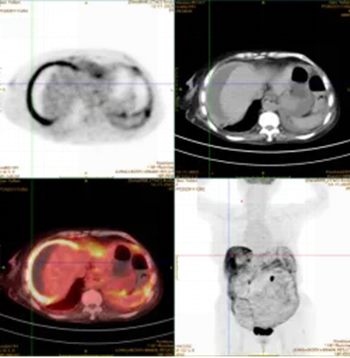

外院曾行诊断性腹腔穿刺,却未能明确病因。PET-CT检查提示恶性肿瘤可能。为寻求进一步诊治,家属来到医院胃肠甲状腺外科找到杨战锋主任。

杨主任团队详细评估后,决定行腹腔镜探查。术中发现腹膜、大网膜及肠壁表面布满大小均匀的粟粒样结节,腹腔及盆腔内积聚大量草绿色腹水。凭借丰富经验,杨主任判断该病变可能并非肿瘤,留取病理标本后结束手术。

术后病理结果出人意料:检测出结核分枝杆菌,最终确诊为结核性腹膜炎。 患者随后转入感染科接受抗结核治疗,目前恢复良好。